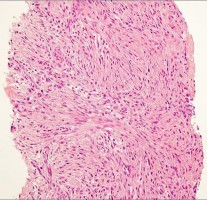

A 35-year-old female is diagnosed with a locally aggressive giant cell tumor of the distal radius. Preoperative administration of Denosumab is planned to facilitate downstaging and joint-salvage surgery. What is the exact mechanism of action of Denosumab in this context?

Explanation

Denosumab is a fully human monoclonal antibody that specifically binds to RANKL (Receptor Activator of Nuclear factor Kappa-B Ligand). By binding to RANKL, it prevents it from interacting with the RANK receptor on the surface of osteoclasts and osteoclast precursors. In Giant Cell Tumor of bone, the neoplastic mononuclear stromal cells express high levels of RANKL, which aggressively recruits and activates the reactive multinucleated giant cells (osteoclasts) that cause bone destruction.